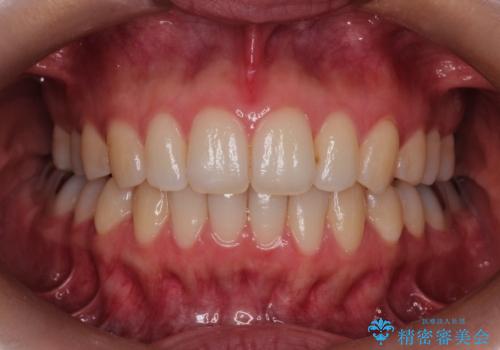

見た目、嚙み合わせ及び、治療期間や施術内容に大変ご満足いただきました。